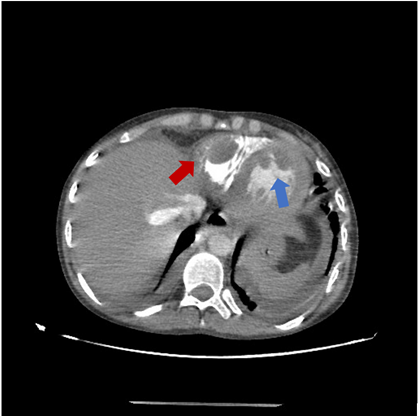

A 19-year-old female patient, treated for Juvenile Lupus complicated of Lupus nephritis class IV , was admitted with fever and shortness of breath. Clinical examination revealed an orthopneic patient with lower limb edema and bilateral crackles at lung bases. Electrocardiogram showed negative T waves in the septo-apical and inferior leads. Laboratory findings revealed impaired renal function, normochromic normocytic anemia, and normal coagulation parameters with low titer of antiphospholipid antibodies. Thoracic computed tomography angiography ruled out pulmonary embolism and detected three well-defined masses regular contours (Figure 1).

Figure 1: Thoracic angiographic scan showing 2 masses at the apex of the left ventricle (blue arrow) and a third one at the lateral wall of the right ventricle (red arrow).